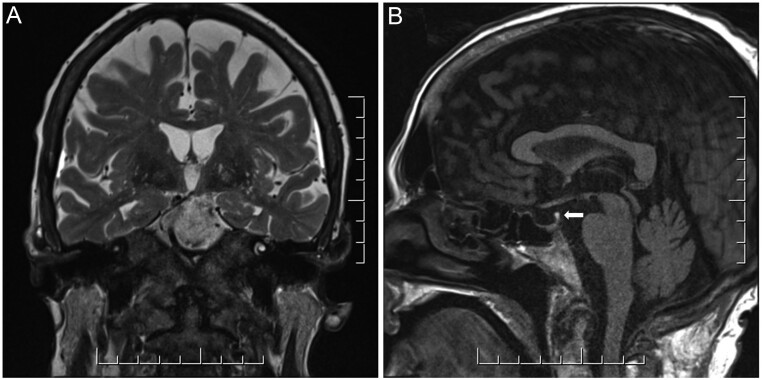

The patient completed an initial course of induction chemotherapy with cytarabine and daunorubicin. The oncology service additionally recommended twice weekly intrathecal chemotherapy, of which she tolerated four doses. Her post-induction bone marrow biopsy and flow cytometry indicated disease remission. A repeat MRI of the brain with gadolinium following chemotherapy showed resolution of the previously noted T2-hyperintensity and return of the pituitary bright spot (Fig. 2). Despite resolution on imaging, her CDI persisted requiring maintenance on sublingual desmopressin 120 µg twice daily. Missed doses of her desmopressin while in an intermediate care facility caused a recurrence of her previous symptoms with hypernatremia up to 158 mmol/L which resolved with re-initiation of desmopressin therapy.

Figure 2.

MRI of the brain showing resolution of the previously seen increased signal at the hypothalamus and mamillary bodies on T2-weighted image (A) and return of the pituitary bright spot (B) following chemotherapy.